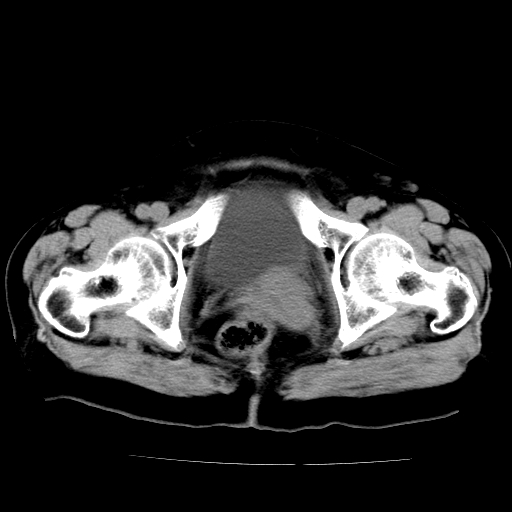

女,73岁,阴道流血一周。

宫颈不规则增大;结合临床考虑宫颈癌。建议作mri检查

1\\老年妇女突发阴道流血,常见病考虑宫颈癌.本病例宫颈部显示形态不规则,密度欠均匀,支持考虑宫 颈癌,建议mri 或阴道超声坚持

2\\但是盆腔两侧尚未见到明显肿大淋巴结等转移征象

宫颈不规则增大,左后方可见结节状突起.支持宫颈癌.

宫颈壁明显增厚,左侧为甚,宫颈癌待排,建议宫颈涂片细胞学检查。

宫颈不规则增大,周围脂肪间隙毛糙,结合临床考虑宫颈癌,盆腔内未见肿大淋巴结。